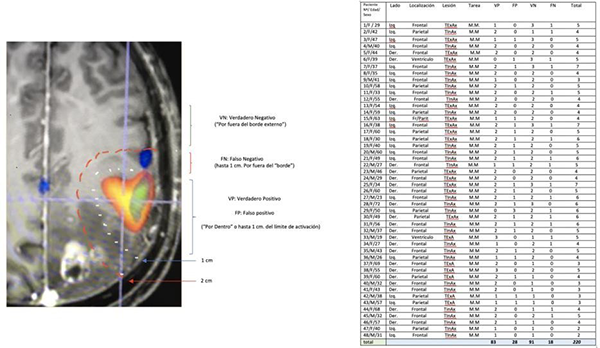

Las respuestas a la ECD (Estimulación Cortical Directa) se clasificaron en este trabajo como: 1 (VP): verdadero positivo: cuando se observa respuesta motora por ECD dentro del área de activación de la RMfm, o hasta un máximo de 1 cm por afuera del “borde”, 2 (VN): verdadero negativo cuando hubo ausencia de respuesta por fuera del “borde” del área de activación de la RMfm,    (3)FP: falso positivo ausencia de respuesta motora por ECD dentro del área de activación de la RMfm (ó su borde), 4: falso negativo la presencia de respuesta motora por ECD 1 cm por fuera del “borde del área de activación BOLD.

Resultados de la prueba (Tabla Nº1)

Se realizaron un total de 220 (tabla Nº2) registros luego las respuestas se distribuyeron para su análisis estadístico en una tabla 2 x 2 (tabla N° 3):

Tabla Nº2

Tabla Nº3